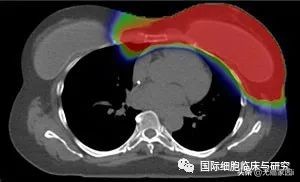

注:红色:高辐射剂量;绿色:中间辐射剂量;蓝色:低辐射剂量

图片依次为质子治疗(上图)和常规X射线疗法(下图)